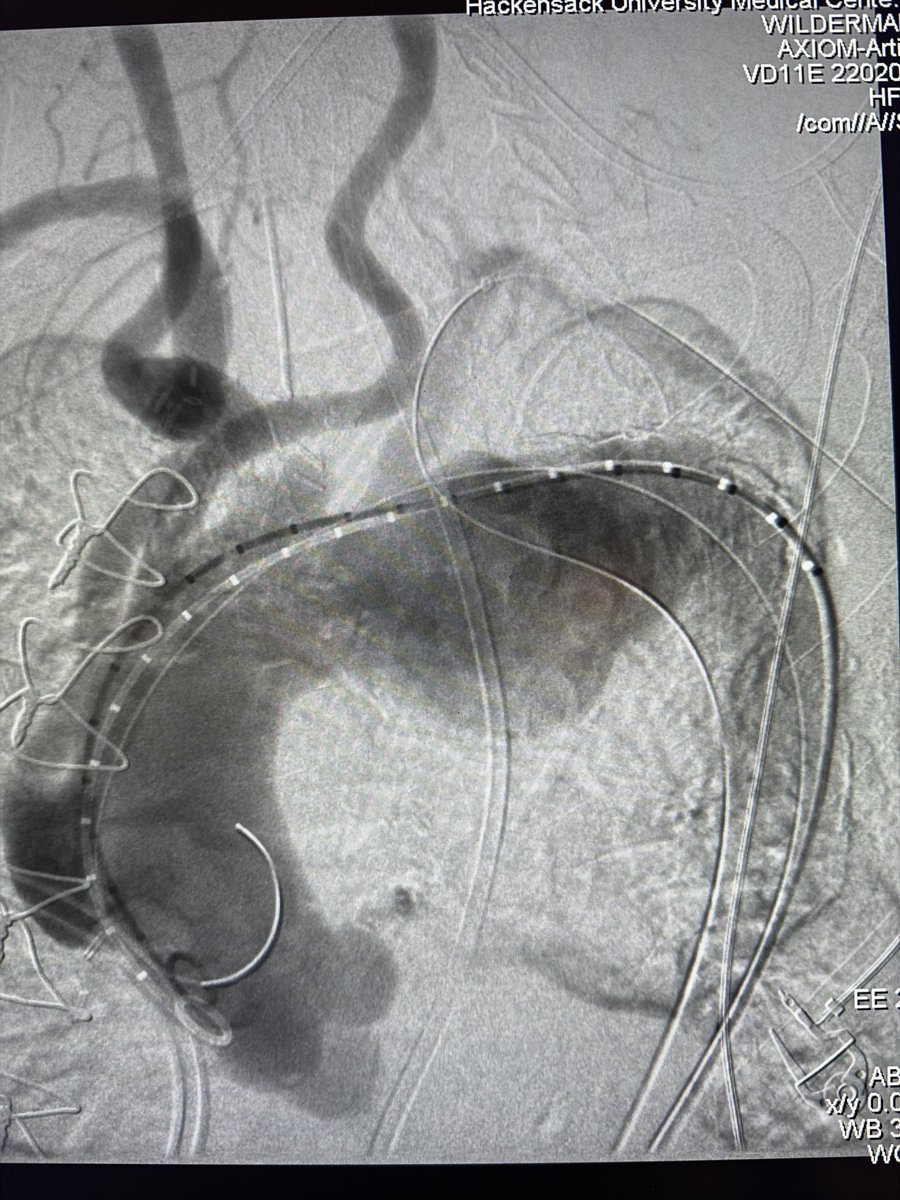

Dr Michael Wilderman

Chief of Endovascular Surgery and Co-Director of Aortic Center at Hackensack University Medical Center